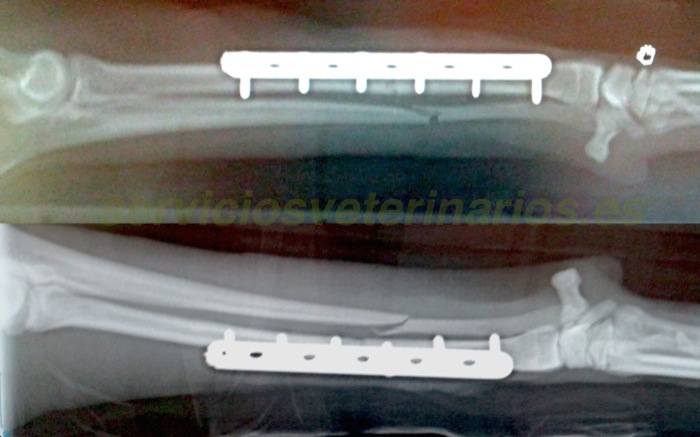

| Diagnóstico | Fractura bilateral de radio y cúbito diafisaria media transversa con desplazamientos de los focos de fractura superpuestos. |

| Tratamiento | En las fracturas bilaterales el material de osteosíntesis se elige algo mas resistente y en este caso se opta por placas de 2mm de grosor y con tornillos sobre agujeros alternos dado lo delicado del hueso con el que toca trabajar. |

Hoy estamos de suerte porque la mayoría de veces tenemos unas fracturas más complicadas con esquirlas, fisuras, fragmentos distales muy cortos y grandes daños en los tejidos blandos. En este radio izquierdo la fractura es transversa media diafisaria con tamaño de los fragmentos suficiente para trabajar cómodamente.

Esta radiografía del miembro derecho también nos presenta una fractura limpia. Como siempre antes de entrar en quirófano se tienen tomadas un amplio número de distancias y diámetros óseos que nos ayuda a elegir mejor el material a implantar durante la cirugía así como acortar el tiempo quirúrgico.

En el miembro derecho se puede reducir más fácilmente el foco de fractura, no ha costado tanto enfrentar de nuevo los fragmentos y se puede colocar la placa primero y todos los tornillos después. Por supuesto esta opción (presentar primero la placa) no requiere calcular tan cuidadosamente la posición de los primeros tornillos que de no ser perfecta condicionaría una incorrecta alineación de la fractura.

La resolución es satisfactoria. El alineamiento del miembro izquierdo operado en principio sin presentar la placa también es correcto y tras despertar se recupera rápidamente tras las casi 2 horas de cirugía de los dos miembros.

Estas radiografías de control están realizadas el día 14. Todo evoluciona bien a pesar de que ya salta del sillón. Como en otros casos se insiste por parte del equipo al propietario sobre las medidas de control (espacio reducido y sin alturas en casa y atado corto en los breves paseos). Ante el poco control esperaremos aún 7 días y retiraremos la férula que refuerza los vendajes Robert Jones. En caso de haber podido mantener, desde el día 1, el animal en una jaula de 1-2 metros cuadrados, o control similar, el proceso para permitir el apoyo sería mucho mas rápido y no llegaríamos a la debilidad y cierta atrofia muscular que tendremos sin duda más adelante.

Este es el control al mes tenemos una alineación perfecta a la espera de que suelde. El cúbito se ha movido mínimamente y presenta un escalón menor al mm, el ancho total del cúbito es de 2,7 mm en este punto. En este momento (día 30) retiramos las férulas y, ante el poco control sobre el animal, se le deja un Robert Jones en cada miembro que permitirá en breve una leve flexión de carpo y codo.